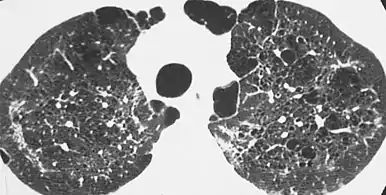

| CT scan of the lung showing bullae in the lower lung lobes of a subject with type alpha-1-antitrypsin deficiency. There is also increased lung density in areas with compression of lung tissue by the bullae. | |

- A bulla has a wall thickness of less than 1 mm.[2] By radiology definition, it has a total size of greater than 1 cm.[3] By pathology definition, it originates in the lung parenchyma (rather than in the pleurae).[4]